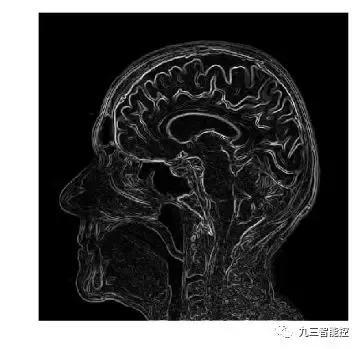

(5)大脑核磁共振图像(侧面)

边缘检测(梯度模)

图像的梯度模的定义如下,它可以同时检测图像的水平和垂直方向的变化。